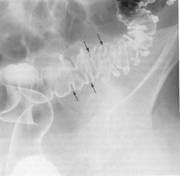

Fig. 234 Diverticolii colonului

Radioimagistic, apar ca imagini de plus de substanta baritata cu colet, au structura omogena, sunt bine delimitati.

Diverticolii pot fi congenitali, avand toate straturile peretelui colic, sau dobanditi; se localizeaza la nivelul anumitor segmente ale colonului (sigmoid) sau pe tot cadrul colic.